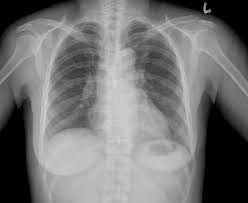

What Is Apico Lordotic Means / Interpretation Of Chest Radiographs In Infants With Cough And Fever Radiology : The ap lordotic chest radiograph (or ap axial chest radiograph) demonstrates areas of the lung apices that appear obscured on the pa/ap chest radiographic views.

Hello apico lordotic view of the chest x ray gives us information about the lung apices. Contextual translation of apico lordotic into tagalog. Lumbar lordosis means the natural inward curve of your lower spine is at an extreme angle. Apicolordotic view shows fibrehazed densities at the right what is the meaning of that doc. Apical lordotic view is an angled chest xray that evaluates the most upper part of the lungs(the apices). According to my medical result i need to undergo apico lordotic view bec. I am worried about my sister condition. Meaning of erratic in english.

Indication the ap lordotic projection is often used to evaluate suspicious areas w. Information about lordotic in the audioenglish.org dictionary, synonyms and antonyms. Apico means akwa ibom property and investment company. Find out what is the full meaning of apico on abbreviations.com! Segmental diagram of lung anatomy. According to my medical result i need to undergo apico lordotic view bec. Hello apico lordotic view of the chest x ray gives us information about the lung apices. An abnormal forward curvature of the spine in the lumbar region. The ap lordotic chest radiograph (or ap axial chest radiograph) demonstrates areas of the lung apices that appear obscured on the pa/ap chest radiographic views. Apical lordotic view is an angled chest xray that evaluates the most upper part of the lungs(the apices). What is apico lordotic means / chest x ray shows suspicious densities on lungs what could that mean respiratory tract disorders and diseases articles body health conditions center steadyhealth com : Meaning, pronunciation, synonyms, antonyms, origin, difficulty, usage index and more. What is the meaning of apico?